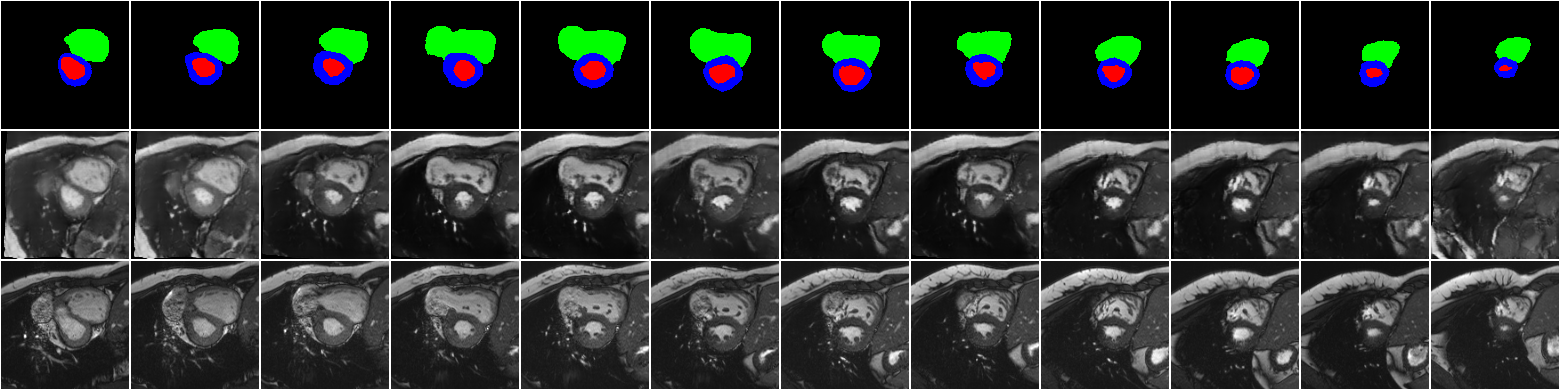

The main results, which are the synthetic images corresponding to the XCAT labels are shown in \figurereffig:synth_frame_0-12_base. For visualization purposes, we fix the location and vary the time frame. The results for 12 time frames from end-diastolic to end-systolic phase (from left to right) are shown at the base location of the short axis view of the heart. Due to limited space, similar results for other time frames and locations are shown in A, \figurereffig:synth_frame_0-12 and \figurereffig:synth_frame_12-24. Additionally, a 4D visualization of our results is available here: \urlhttps://bit.ly/2REVAzB. As seen in these figures, for a fixed location, the classes of interest are generated according to the input label map, while the background is consistent and coherent.

fig:synth_frame_0-12_base

Similarly, the results for end-systolic to end-diastolic phases, corresponding to apex, middle and base locations are shown in \figurereffig:synth_frame_12-24.

fig:synth_frame_12-24

\subfigure[The apex location][c]

\subfigure[The mid location][c]

[The base location][c]